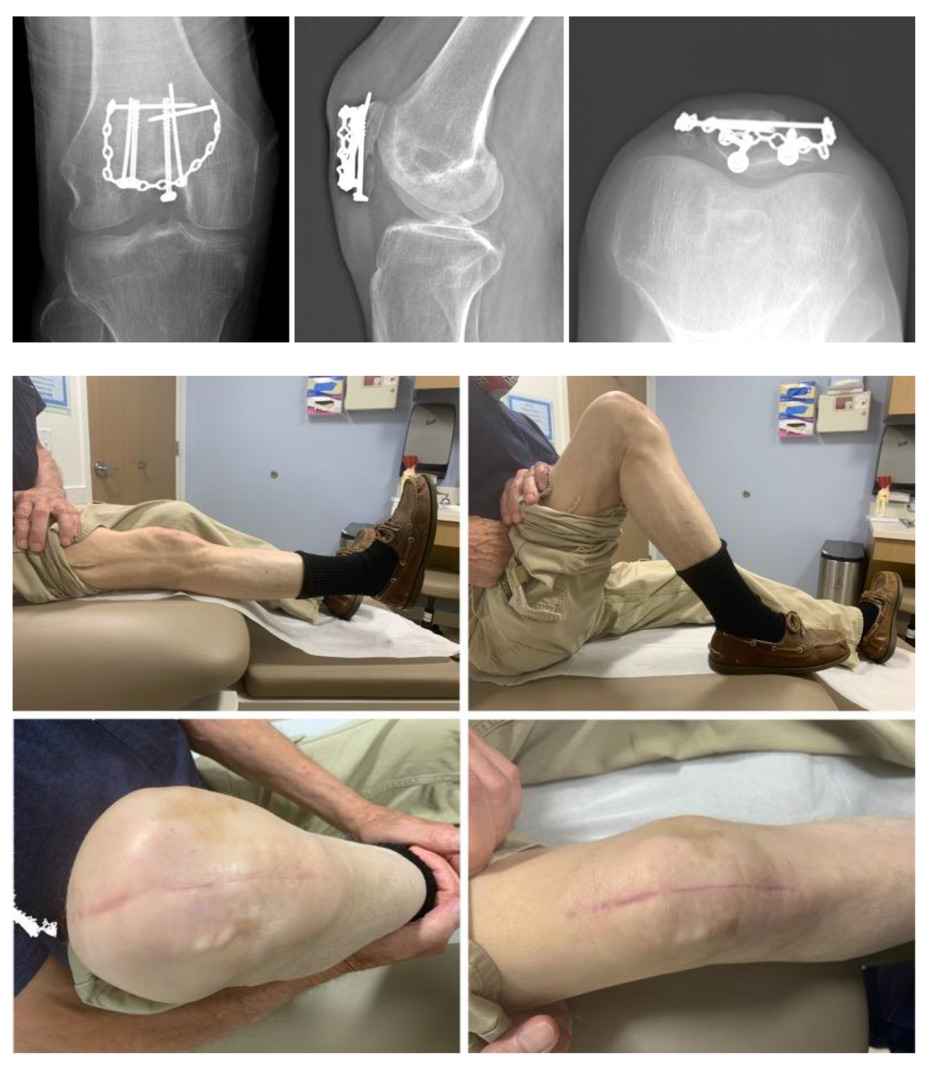

Patellectomy as a Salvage Procedure top, Post patellectomy patellar tendon dislocation An unusual injury top, Traumatic quadriceps rupture in a patient with patellectomy a top, A 66 year old male visited our clinic with right knee p Open i top, PDF Partial Patellectomy A Series of 17 Patients Semantic Scholar top, Patellectomy for osteoarthritis a new tension preserving surgical top, Total Patellectomy top, Patellectomy a debated Chaitanya Accident Hospital top, PDF Partial Patellectomy A Series of 17 Patients Semantic Scholar top, Extensor Mechanism Injuries of the Knee Musculoskeletal Key top, Lateral radiograph status post complete patellectomy. Download top, Treatment of a comminuted patella fracture with a patella rim top, Patellectomy Musculoskeletal Key top, Comparison of total patellectomy and osteosynthesis with tension top, Unicondylar knee arthroplasty following a patellectomy ScienceDirect top, Total knee arthroplasty in patients with a previous patellectomy top, Patella Fracture Trauma Orthobullets top, PDF Partial Patellectomy A Series of 17 Patients Semantic Scholar top, Total knee arthroplasty in patients with a previous patellectomy top, Total patellectomy with extensor mechanism reconstruction top, Total patellectomy with extensor mechanism reconstruction top, Total Patellectomy Technique Orthopedic Implants Industry in top, Illustration showing the rabbit partial patellectomy and top, Unicondylar Knee Arthroplasty in Patellectomized Patients top, Comparison of total patellectomy and osteosynthesis with tension top, Partial Patellectomy Surgical Technique top, Unicondylar knee arthroplasty following a patellectomy ScienceDirect top, A 71 year old woman with extensor mechanism instability after top, Comparison of total patellectomy and osteosynthesis with tension top, Long term outcomes after partial patellectomy in comminuted top, Patellectomy Radiology Case Radiopaedia top, Comparison of total patellectomy and osteosynthesis with tension top, Comparison of total patellectomy and osteosynthesis with tension top, Long term outcomes after partial patellectomy in comminuted top, Patellectomy for osteoarthritis a new tension preserving surgical top, Product Info: Patellectomy top